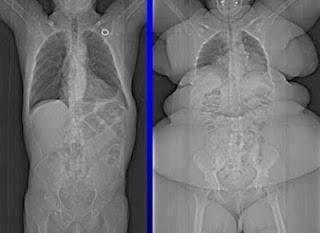

The myth of being "big boned"

Let's be very clear on this; there is no such thing as "big boned". Studies have shown that the bone size and density of a "big boned" person is almost the exact same as as a "normal" person (being truly "big boned" only accounts for about 10lbs). So if you've been using that as your excuse ....or one of your excuses, it's time to let it go and realize that the reason you are overweight is because you let yourself get that way. Of course there are extenuating circumstances for some; you were raised in an over-weight family and learned bad eating habits before you even knew about them. But the fact that you got overweight and the fact that you've let yourself stay overweight are two completely different things. There might be some extenuating circumstances for how you got to this point... I know there was for me, but there is no excuse for allowing yourself to stay overweight, other than you.